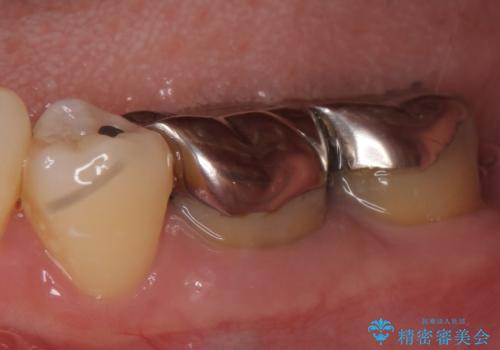

- 左下の奥歯が激しく痛むので診て欲しいといらっしゃった方の症例です。

左下7番目の歯に根尖病変を認めたため、再根管治療を行いました。

症状の消失を確認後、オールセラミッククラウンによる補綴を行いました。